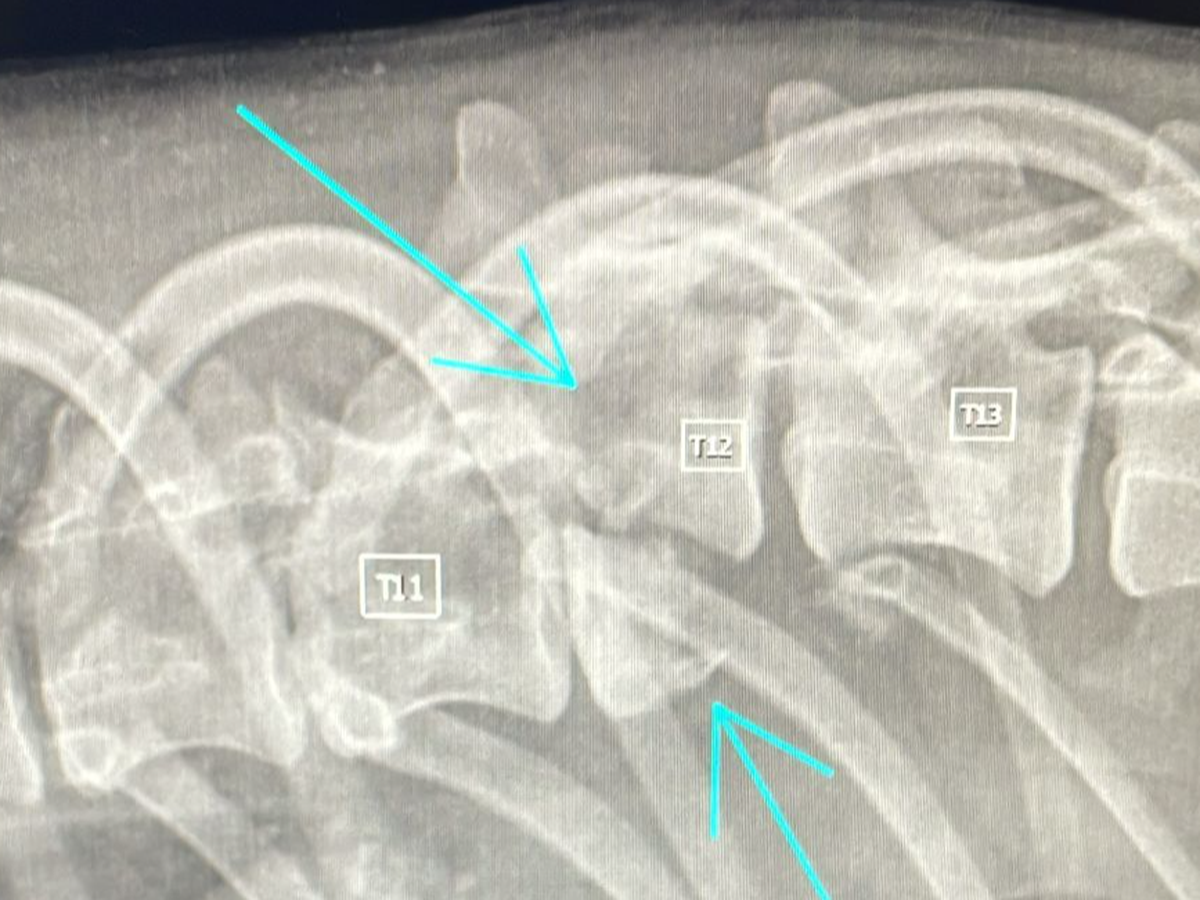

Come ho già scritto chappy ha Una lussazione di colonna, ciò significa che potrà condurre una vita da cane paraplegico a vita e che non tornerà a camminare con le sue zampe ad eccezione di un tentativo di sviluppo di andatura spinale ma non c'è certezza che questo avvenga.

Tecnicamente dopo intervento di stabilizzazione colonna vertebrale+ lunga fisioterapia in acqua si potrebbe verificare la possibilità di andatura spinale o nella peggiore delle ipotesi carrellino a vita.

Ad oggi non c'è certezza sul fatto che potrà avere un recupero e prima di finire in sala chirurgica con un intervento sarebbe opportuno effettuare una Tac da lì decidere di operare o eutanasia.